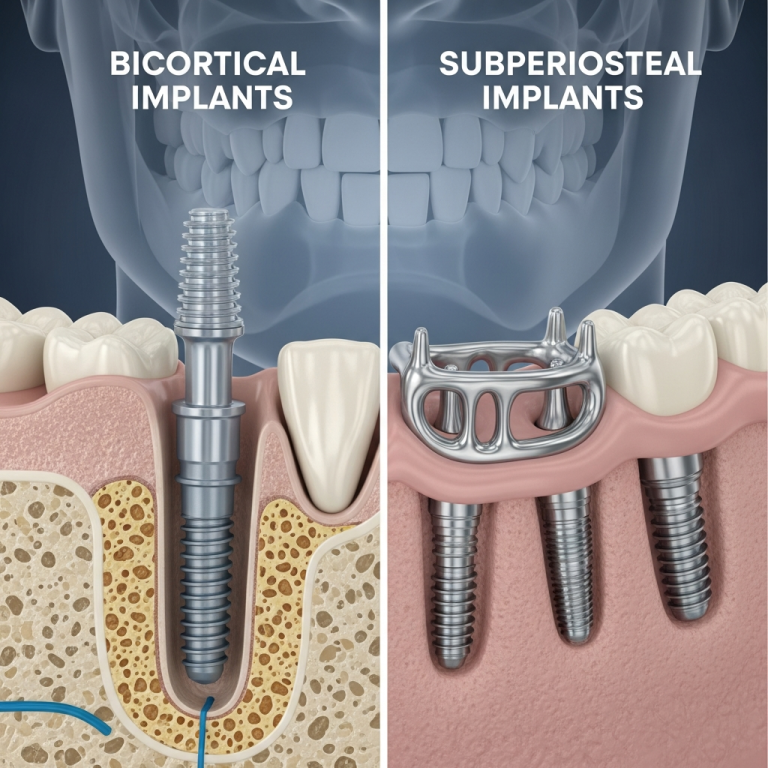

Cât costă implanturile fără os (bicorticale) în România în 2026? Prețuri reale și ce influențează costul

Implanturile bicorticale rămân una dintre cele mai eficiente soluții raport calitate-preț pentru pacienții cu os redus, deoarece elimină costurile mari ale grefelor osoase și sinus lift-ului.